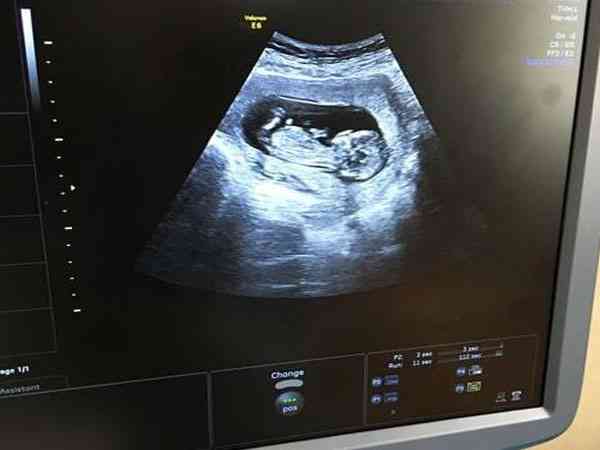

nt值看男孩女孩一般是通過生殖器部位和脊柱下部角度、胎兒姿勢以及nt資料等來判斷胎兒性別,nt圖和nt單資料是通過醫學檢查方法得出的結果,這也是這種方法比較流行的原因。但是這種方法並不準確,nt檢查是通過檢查胎兒頸項透明帶的厚度,可以在早期診斷出胎兒是否有脊柱裂、腦積水等先天性疾病,所以這種方法不能做為判斷胎兒性別的依據。從nt單子看男女是國外比較流行的判斷胎兒性別的方法,nt值看男孩女孩訣竅也有很多,一般是通過生殖器部位和脊柱下部角度、胎兒姿勢以及nt資料等來判斷胎兒性別,nt圖和nt單資料是通過醫學檢查方法得出的結果,這也是這種方法比較流行的原因。其實這種方法並不準確,nt檢查是通過檢查胎兒頸項透明帶的厚度,可以在早期診斷出胎兒是否有脊柱裂、腦積水等先天性疾病,這種方法不能做為判斷胎兒性別的依據。

nt檢查不能判斷胎兒性別,只是滿足了孕媽們對寶寶的好奇心,雖然不提倡孕媽們依賴這種手段去判斷寶寶性別,但好奇寶寶性別的孕媽不妨可以用這種方法來試一試,接下來詳細的介紹一下通過nt單子看男女的幾種方法,具體如下: